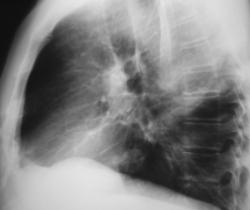

В сентябре 2008 года пациент был направлен на профилактическую флюорографию.

Иллюстрация 2. По флюорограмме, произведенной в прямой стандартной проекции, было отмечено некоторое уплотнение тени правого корня в области тела в виде тонкой лентовидной тени. Справа медио-базально и в области сердечно-диафрагмального синуса определяется снижение прозрачности легочной ткани в виде фокусной тени средней интенсивности с нечеткими контурами. Структура тени по флюорограмме оценена, как неоднородная.

Иллюстрации 3, 4 – фрагменты флюорограммы (с увеличением изображения), демонстрирующие фокусную тень, локализующуюся справа медио – базально. Пациент «взят на контроль».